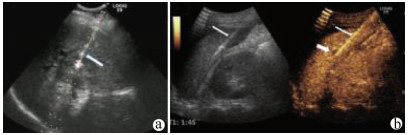

Guideline for ultrasonic diagnosis of liver diseases

Chinese Society of Ultrasound in Medicine, Oncology Intervention Committee of Chinese Research Hospital Society, National Health Commission Capacity Building and Continuing Education Expert Committee on Ultrasonic Diagnosis

2021, 37(8): 1770-1785. DOI: 10.3969/j.issn.1001-5256.2021.08.007

Abstract(3025) HTML (6526) PDF (9311KB)(794)

Abstract:

Ultrasound is a non-invasive, real-time, inexpensive, radiation-free and easily repeatable method, usually used for liver imaging. In recent years, new ultrasound examination techniques for liver diseases such as contrast-enhanced ultrasound and elastography have been rapidly developed, which can effectively identify intrahepatic space-occupying lesions, assess the degree of liver fibrosis and portal hypertension, and monitor the effects of treatment. Therefore, these technologies play an important diagnostic role in clinical liver diseases and have therapeutic interventional value. This guideline classifies the instrument set-up, patient preparation, and physician examination methods through multimodal ultrasound examinations (gray-scale ultrasound, color Doppler ultrasound, contrast-enhanced ultrasound, elastic ultrasound) for liver diseases. In addition, liver diseases multimodal ultrasound technology diagnostic criteria for diffuse hepatic lesions (inflammatory lesions, fibrosis, and sclerosis), multiple space-occupying lesions, and interventional procedures have been defined and standardized. Concurrently, we also recommend the ultrasound monitoring time interval and diagnostic report writing standard for liver diseases.